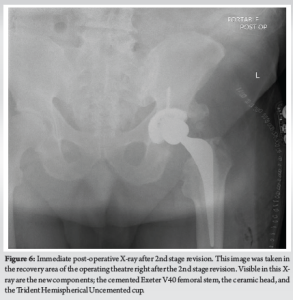

A 76 year old with a BMI of 36 kg/m2 male presented to the Emergency Department with left-sided hip pain and discomfort after performing a “twisting” motion of his hip while getting into bed. He described a “popping” sensation in his left hip upon doing this movement and immediately experienced a sharp pain and was unable to weight bear on that side. The patient described a discomfort in that left hip for the last 4 weeks before this acute presentation, which was not triggered by any trauma/injury. This patient had a MoM THA that was performed 16 years ago for osteoarthritis. He had had a successful outcome until now and denied any post-operative complications after the procedure. The MITCH TRH Modular head with an Exeter V40 cemented stem was used and the operation performed by an experienced consultant orthopedic surgeon. The patient’s medical history includes atrial fibrillation, coronary stenting, high BMI (36 kg/m2) hypertension, hypercholesterolemia, and bilateral total knee replacements. The patient is a non-smoker with occasional alcohol intake and mobilizes independently without walking aids at baseline. Clinical examination at the presentation revealed a shortened limb on the left side held in the neutral position. The patient was unable to straight leg raise due to pain and had a normal neurological and vascular examination. No visible signs of injury or trauma were present, and a systems examination was normal. The patient was admitted under the care of the orthopedic team, and investigations, including X-rays, MARS scan, laboratory tests (Full blood count, renal profile, C-reactive protein, coagulation profile, metal ion levels), and electrocardiogram, were ordered. X-rays (Figs. 1 and 2) revealed head-stem dissociation in a MoM hip configuration. Blood investigations were within normal levels and without any evidence of infection. Of note, metal ion levels are still in process. A MARS scan was conducted which revealed a subfascial 7cm × 7 cm × 10 cm collection posterior to the THA (Fig. 3.)

The operation was carried under general anesthetic due to difficulty in spinal anesthesia. The patient was placed laterally on the operating table with front and back supports and given 1 g IV tranexamic acid and 1.5 g IV cefuroxime before skin incision. Skin preparation and draping were done in the standard fashion and a posterior approach was used to expose the hip joint. Extensive metallosis was noted covering muscle and fascial tissue (Fig. 4) which was carefully debrided during the surgery. Examination of the stem revealed asymmetrical wear patterns of the trunnion and oxidation of the neck and body of the stem (Fig. 5). All original components were explanted, and a non-articulating cement spacer was inserted into the joint. Although no pus was noted in the joint, the concern of infection remained, and multiple samples of tissue and fluid were taken for culture and sensitivity throughout the procedure.